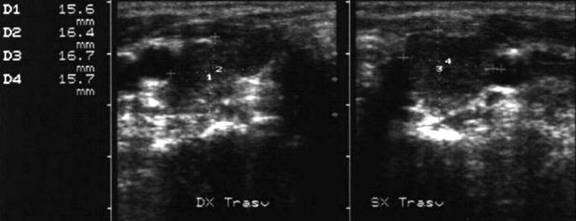

Voluminoasa tumefactie laterocervicala dreapta (16 cc ) si paratraheala stanga

(3 cc), pozitiva la citoaspiratie pentru recidiva de neoplazie papilara.

Aceeasi de

65 ani. Nu se evidentiaza vascularizatie intratumorale

Femeie de 29 ani. Linfonodul in regiunea

laterocervicala dreapta ( 7x12x23mm, 1 cc) in neoplazie papilara a tiroidei. Structura

parenchimatoasa, neomogenea, cu margini

nete, cu absenta hilului.Examen citologic: metastaza de neoplazie papilara.

Lob drept,

proiectie trasversala si longitudinala

Aceeasi pacienta. Nodul de consistenta dura in lobul

drept spre istm.

Ecografia: nodul cu margini indistinte care deformeaza marginea anterioara a glandei,

parenchimatoasa, neomogena, hipoecogena. Prezenta de linfonodi laterocervicali.

Ctoaspiratie: carcinom papilar.

Femeie de 48 ani. Metastaza linfonodala

laterocervical stanga voluminoasa (14x26x32mm, 6 cc) de la neoplasm papilar

tiroidian.

Alta metastaza, mai mica ( 9x14mm), laterocervical stanga.

Citoaspiratie pozitiva pentru carcinom papilar.